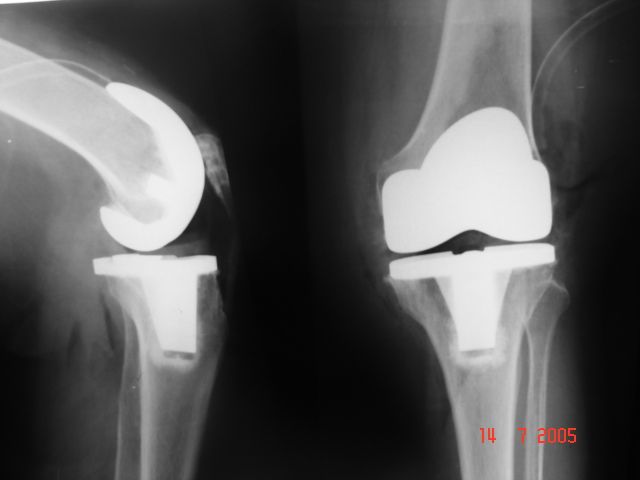

Soy   egresado  de  la  Universidad Autonoma de   Nuevo  Leon. especialidad de ortopedia y traumatologia  en    hospital  numero  21  del  IMSS ne Monterrey  N.L ,con entrenamiento en la  subespecialidad  de   reconstrucion  articular  y  artroscopia  que incluye  lesiones  de  meniscos  , reconstruccion de ligamentos cruzados , lesiones  condrales ,  gonartrosis   tengo  una  historia laboral    institucional de 30  años    hasta el 30  de lulio del 2024 estuve  10  años  en  el  modulo  de  artroscopia  con aproximadamente   1120    artroscopias  de rodilla   y  15 años  en  el  departamento  de    artroplastia  de rodilla  o  de  reemplazos  articulares   ,  los  ultimos   15  años    como profesor  adjunto   y titular  en los cursos    de pre  y posgrados  de  traumatologos  en la  subespecialidad  de  con aproximadamente   160 cirugias  institucionales    en   artroplastia de  rodilla    por  cada año   y  un  numero menor en el  medio particular  dando un total  aproximado  de  2,560  cirugias . de  estas  el  10%    de  revision  y  5%  preotesis    tumorales    de  actualmente   en  funciones  en  el  medio privado  y  acreditado  en todos los  hospitales  de la  localidad  y  con todas  las  aseguradoras   de  gastos  medicos .